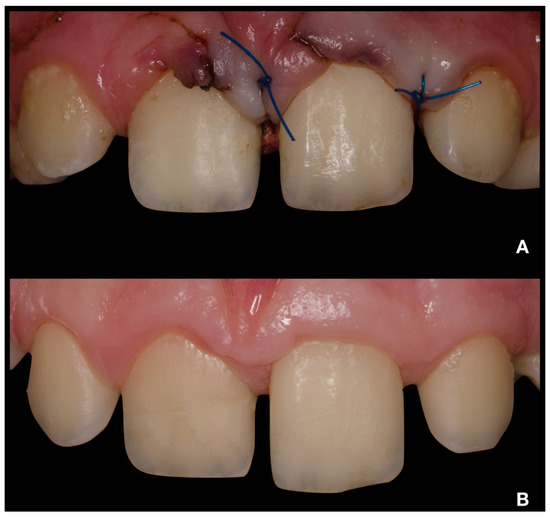

2.3. Deep Pulpotomy and Adhesive Reattachment of Tooth 21 after Flap Reflection

2.4. Follow-Up